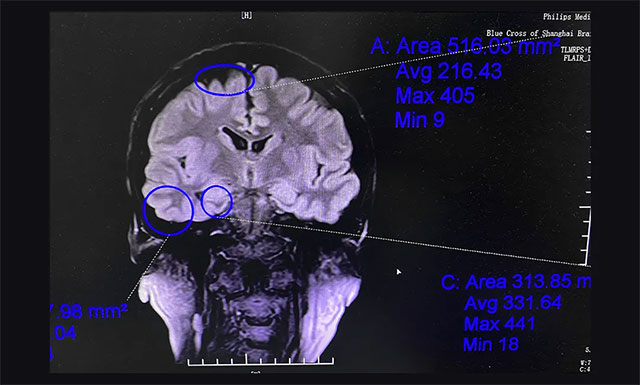

▲ 通過系列檢查評(píng)估,最終明確患者致癲灶

楊忠旭教授團(tuán)隊(duì)通過美國(guó)尼高力視頻腦電監(jiān)測(cè)、核磁共振等評(píng)估,最終明確患者致癲灶為雙側(cè)起源,右側(cè)大腦為主要異常放電起源。手術(shù)指征明確,未見明顯手術(shù)禁忌癥。